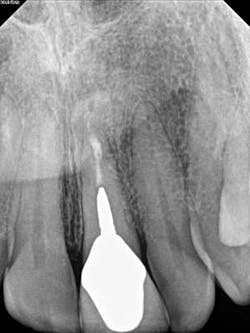

A 52-year-old male patient presented to the office with pain related to tooth No. 9. After radiographic review (figure 4), it was noted that No. 9 had previous endodontic therapy along with a large cast post. The patient was happy with the esthetics of the crown on No. 9, and the clinical and radiographic review showed intact margins and a sound restoration. The recommendation was made to take a narrow-field CBCT image of tooth No. 9. It revealed periapical pathology related to tooth No. 9 that had not broken through the buccal or palatal cortex (figure 5). No fractures were noted and disassembly of the current restoration was not ideal due to the size of the casting in place. The patient was appointed for microsurgical endodontic treatment to save tooth No. 9.